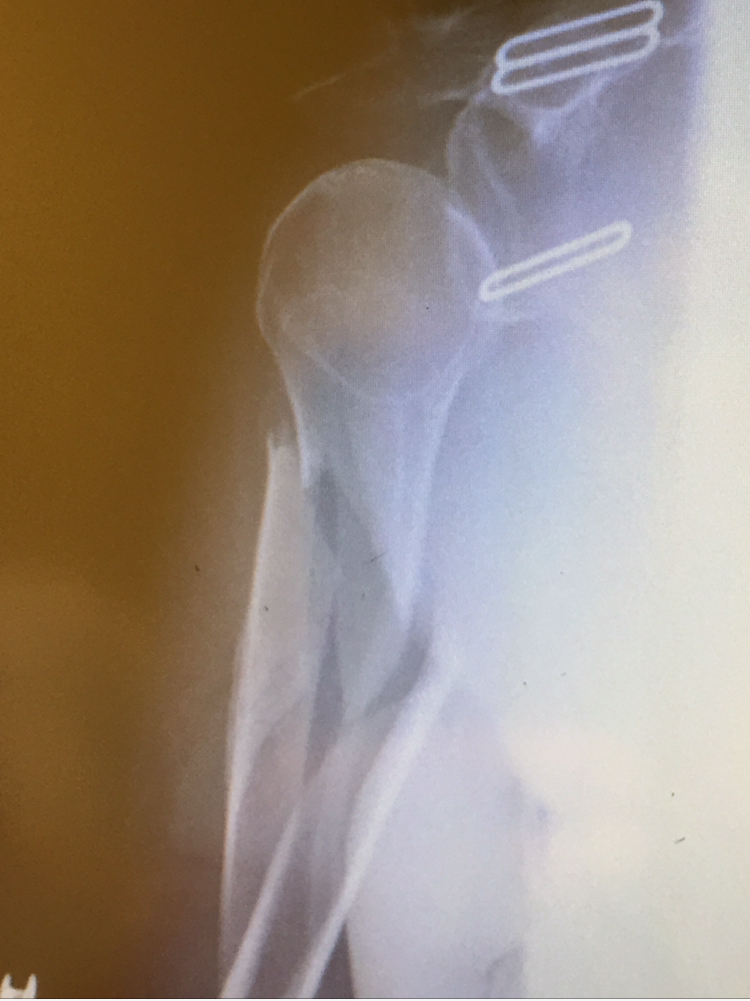

My name is Jayden Cassese and I'm a 12 year old baseball player for the TYA Tigers. In the first pre-season tournament for our big 12U season, I collided with the shortstop sliding into second base and broke off the end of the elbow bone in my left arm. This was the big year for Little League and we had the famous Cooperstown Tournament coming up in July, playing against 100 teams from around the country. I was devastated at the idea of missing that after years of building up to it.

Luckily for us, we knew friends of Dr. Green, and a fellow surgeon at HSS, and both of them strongly recommended we use Dr. Green to repair the elbow. 2 days later I was getting operated on at HSS in Manhattan, and the entire process was handled very well by Dr. Green and his entire staff. After putting 2 pins in my elbow and allowing it several months to heal, while doing PT at HSS along the way, I was able to get back on the field just in time for my big tournament. I came back stronger than ever and hit 2 home runs in one game my first weekend back, then 3 home runs the next week while at Cooperstown! Thank you Dr. Green and team for helping me make it to Cooperstown and beyond.